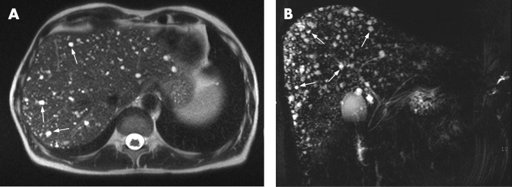

Tại Phòng khám, thăm khám lâm sàng, bác sĩ nhận thấy khối bất thường vị trí hạ sườn trái. Kết quả xét nghiệm chưa phát hiện bất thường. Hình ảnh chụp cắt lớp vi tính ổ bụng phát hiện bệnh nhân có đồng thời hai bất thường bẩm sinh hiếm gặp là lách đôi và ruột xoay bất toàn.

Hình ảnh chụp cắt lớp vi tính phát hiện bệnh nhân có lách đôi

Hình ảnh chụp CT phát hiện bệnh nhân có bất thường ruột xoay bất toàn

Bác sĩ kết luận nguyên nhân gây ra triệu chứng đau bụng vùng thượng vị của bệnh nhân do hội chứng đa lách và ruột xoay bất toàn gây ra.